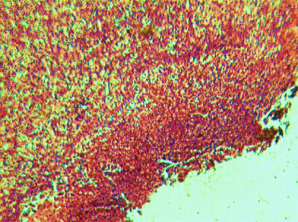

Histological evaluation of gastric lesion

Histological observation showed extensive damage of the gastric mucosa in the ulcer negative control group with necrotic lesions penetrating deeply into the mucosa accompanied by extensive edema and leucocyte infiltration of the submucosal layer (group 2).

Rats that received treatment with aqueous and methanol extracts of the leaves of D. thollonii had comparatively better protection of the gastric mucosa as seen by the reduction of ulcer area, reduced submucosal edema and leucocytes infiltration after 14 days of treatment (fig. 4).

Fig. 4: Histological study of acetic acid-induced gastric damage in rats

In fig. 4: (a’): histological section of a normal control rat: no injuries to the gastric mucosa are seen and the gastric wall is normal. ((b’): histological section of an ulcer negative control rat: there is severe destruction of the surface epithelium and necrotic lesions penetrating deeply into mucosa and submucosa layer. (c’): histological section of rats treated with Maalox (50 mg/kg): the gastric wall appears normally, but there is edema of mucosa and sub mucosa layer.(d’): the histological section of rats treated with Ranitidine (50 mg/kg): the gastric wall appears normally with all layers. (e’): the histological section of rats treated with 125 mg/kg of aqueous extract: there is mild disruption of the sub mucosal layer. (f’): histological section of rats treated with 250 mg/kg aqueous extract: there is moderate disruption of the surface epithelium. (g’): histological section of rats treated with 500 mg/kg of aqueous extract: there is mild disruption of the sub mucosal layer and edema of the muscle. (h’): histological section of rats treated with 125 mg/kg of methanol extracts: there is mild disruption of the epithelium surface and the sub mucosal layer and edema of the serosal layer. (i’): histological section of rats treated with 250 mg/kg of methanol extract: there is mild disruption of the epithelium surface and edema of the submucosal and serosal layers. (j’): histological section of rats treated with 500 mg/kg of methanol extract: there is moderate disruption of the epithelial surface although the gastric wall appears normally.